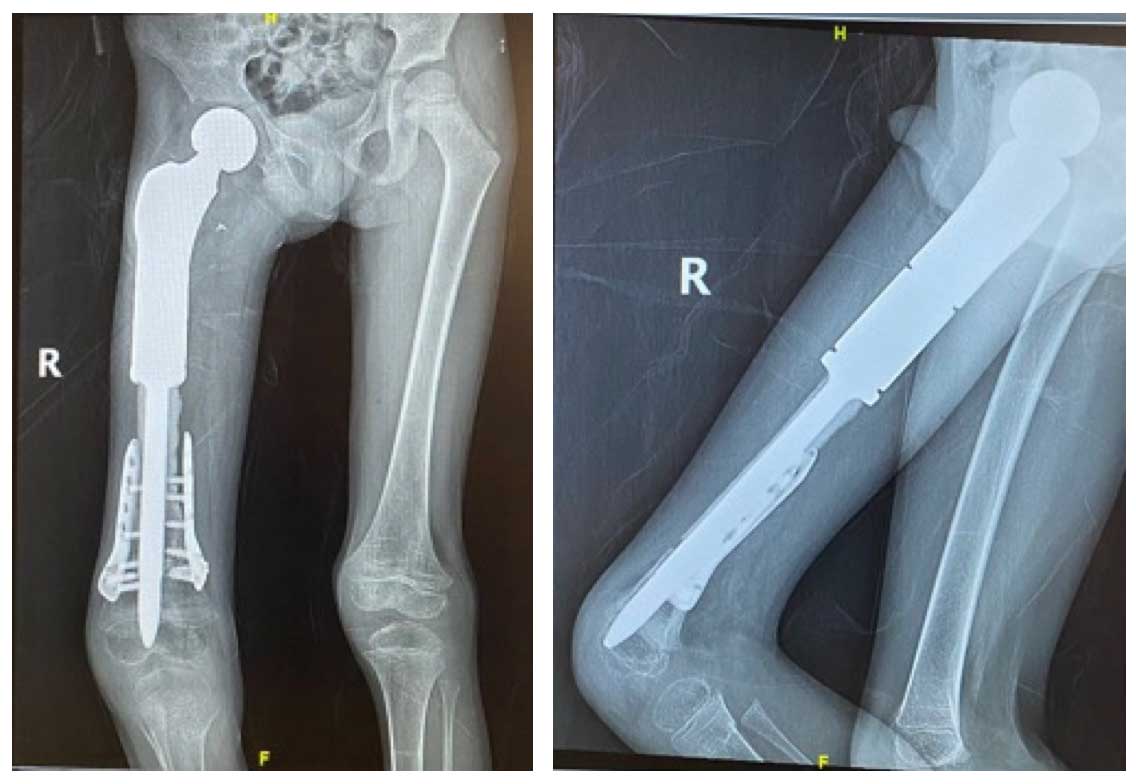

Ameliyat Esnası: Çıkarılan tümör dokusundan ayrılan segmentin sıvı azot ile geri kazanımı sonrası çift plak ile fiksasyonu ve tümör protezinin yerleştirilmesi görülmekte.

Ameliyat Sonrası: Geniş rezeksiyon sonrası geri kazanılan kemiğin çift plak ve tümör protezi ile kombine edilmesi görülmekte.